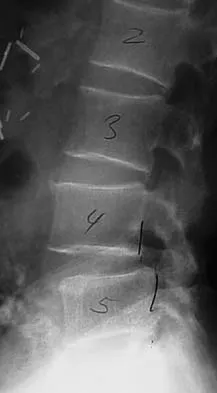

Question 58 High Yield

Figure 33 shows the MRI scan of a 55-year-old woman who has had a 6-week history of back and leg pain. Which of the following clinical scenarios is most consistent with the MRI scan findings at L4-L5?

Detailed Explanation

The MRI scan reveals a L4-L5 foraminal disk herniation originating from the L4-5 disk space that has migrated up into the foramen, compressing the left L4 nerve root. There is normal distribution of the roots in the cerebrospinal fluid, excluding arachnoiditis as a diagnosis, and disk herniation in this location would not result in cauda equina syndrome or myelopathy.